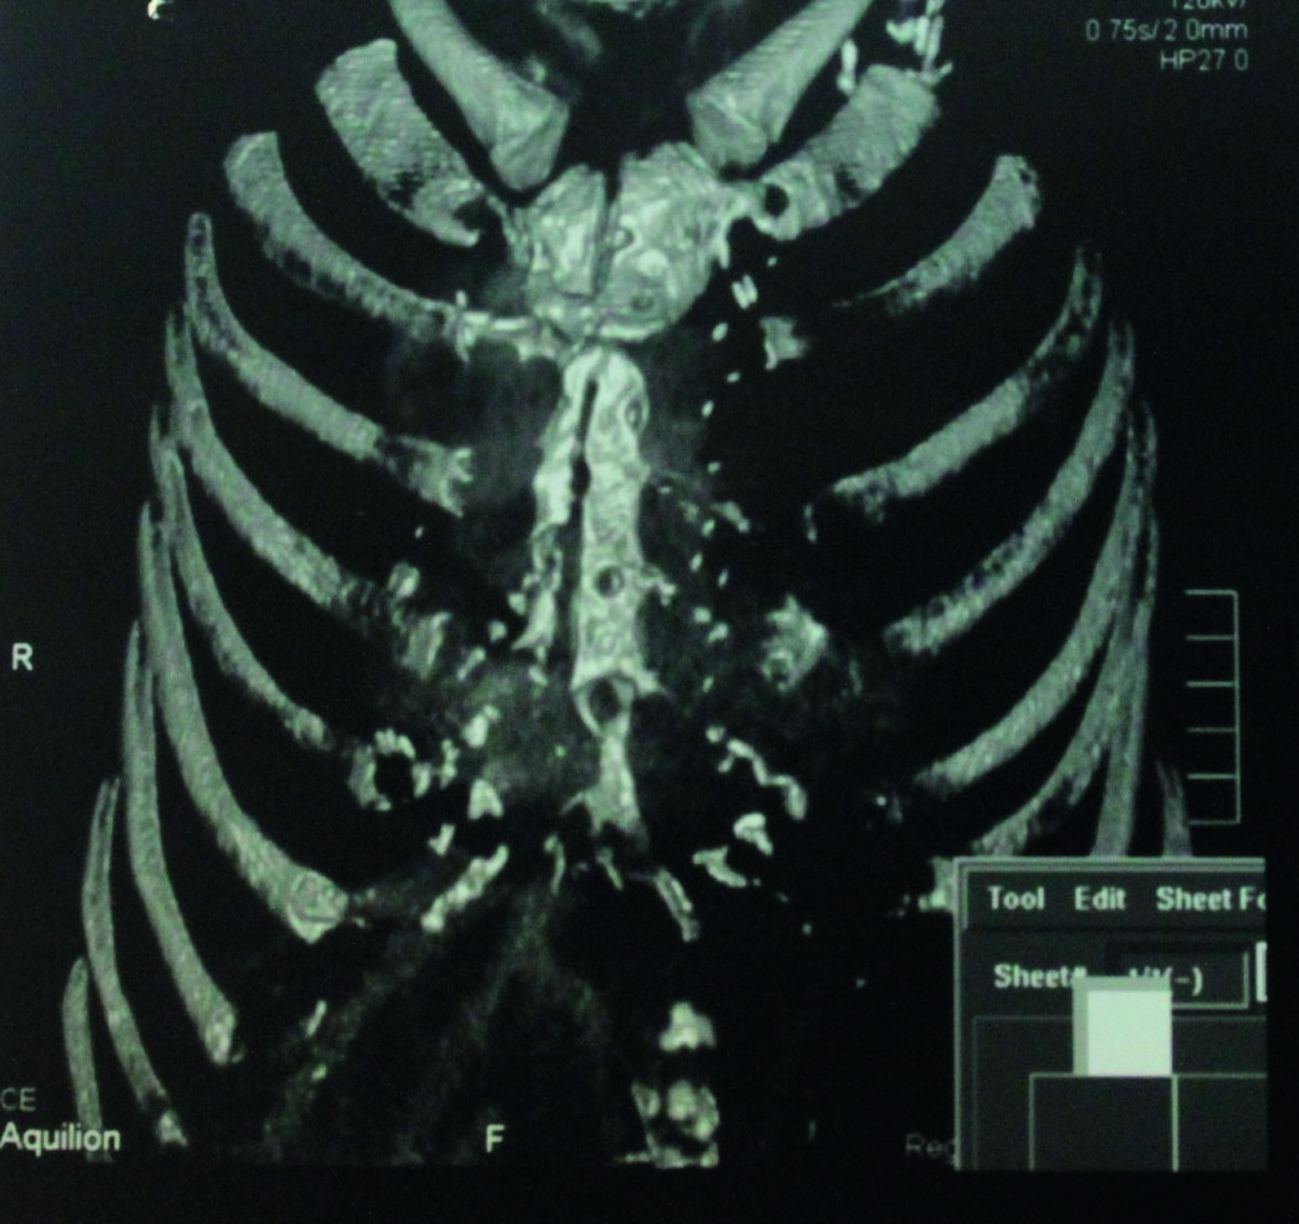

В третьей группе пациентов деструктивные изменения костной ткани (грудина, ребра) до операции были выявлены у 90 (84,9%) пациентов с ПСМ (рисунок 4) и у 25 (86,2%) с остеомиелитом грудины и ребер.

Рисунок 4. Компьютерная томограмма ОГК. Отмечается деструкция и секвестрация створок грудины.

Figure 4. CT imaging of chest. Destruction and sequestration of the sternal cusps.

При этом интраоперационно они были подтверждены только у 106 человек (78,5%). Еще у 9 человек с диагностированной до операции патологией она не верифицирована во время операции. Интраоперационные деструктивные изменения костей выявлены у 104 (98,1%) пациентов с ПСМ и у 13 (44,8%) пациентов с остеомиелитом грудины и ребер (рисунок 5).